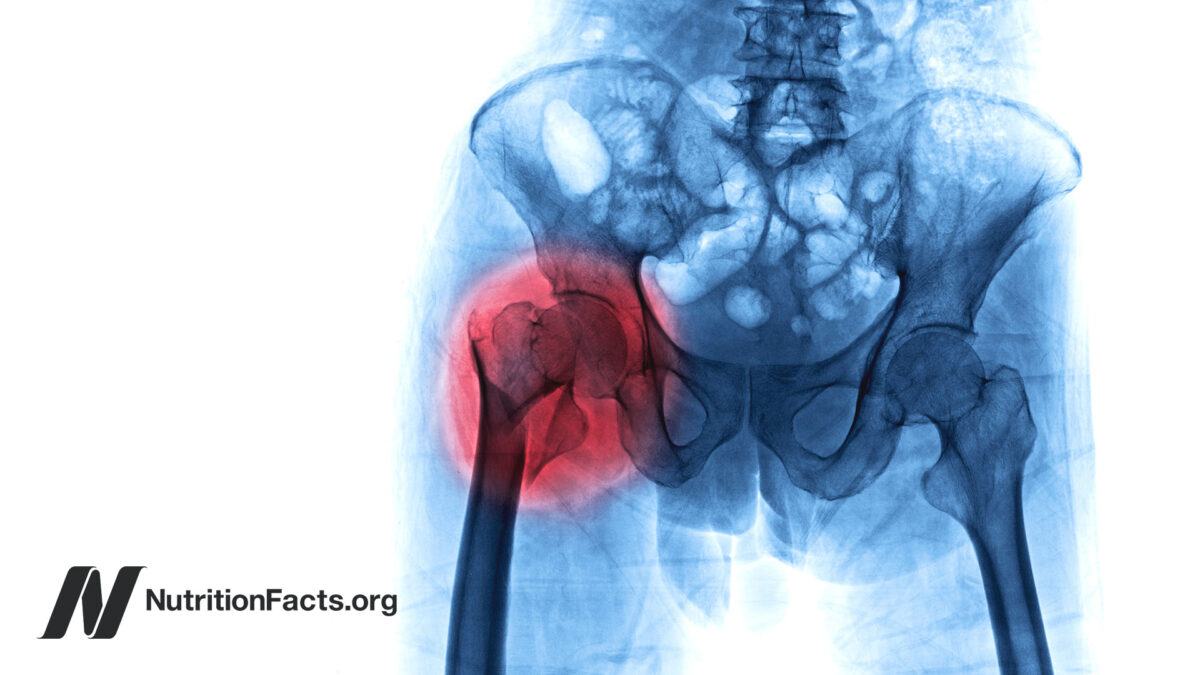

Nearly one in five adults in the world may have osteoporosis. That’s hundreds of millions of people. The word “osteoporosis” literally means porous bone. Now, most of our bone is actually porous to begin with. This is what normal bone looks like inside, but this is osteoporosis.

Bone mineral density is considered to be the standard measure for the diagnosis of osteoporosis. Although the bone mineral density cut-off for an osteoporosis diagnosis is kind of arbitrary, using the standard definition, osteoporosis may affect about one in 10 women by age 60, two in 10 by age 70, four in 10 by age 80, and six or seven out of 10 by age 90. Osteoporosis is typically thought of as a disease in women, but one-third of hip fractures occur in men. The lifetime risk for osteoporotic fractures (for 50-year-old white women and men) are 40 percent and 13 percent, respectively.

The good news is that osteoporosis need not occur. Based on a study of the largest twin registry in the world, less than 30 percent of osteoporotic fracture risk is heritable, leading the researchers to conclude, “Prevention of fractures [even] in the oldest elderly should focus on lifestyle interventions.” This is consistent with the enormous variation in hip fracture rates around the world, with the incidence of hip fracture varying 10-fold, or even 100-fold between countries, suggesting that excessive bone loss is not just an inevitable consequence of aging.

Stomach acid-blocking “proton pump inhibitor” drugs, so-called PPIs—with brand names like Prilosec, Prevacid, Nexium, Protonix, and AcipHex—are among the most popular drugs in the world, raking in billions of dollars a year. But then in 2006, two observational studies out of Europe suggested an association between intake of this class of drugs and increased risk of hip fracture. And by 2010, the growing evidence forced the U.S. Food and Drug Administration to issue a safety alert implicating PPI use with fractures of the hip, wrist, and spine. By now, there’ve been dozens of such studies involving more than two million people who, overall, show higher hip fracture rates among both long- and short-term users at all dose levels.